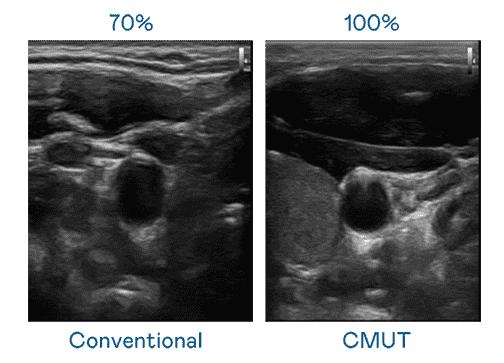

CMUT 技术是一种用电容式微机电元件来产生超音波讯号的技术。。与传统 PZT 压电式技术相比,,,CMUT 频宽增加 30%,,更宽频的超音波讯号让影像解析度大幅提升,,是实现高影像品质医疗超音波扫描、、、促进精准医疗发展的关键技术。。。

大频宽带来超清晰影像

超音波影像的解析度高低,,首先取决于探头能发出的讯号频宽。。。。z6尊龙 CMUT 可提供高清晰的超音波讯号,,,提供高频宽、、、高灵敏度、、、影像纹理细节更高的超音波影像,,,协助医护人员缩短影像判读时间及利用精准的医疗影像进行诊断。。